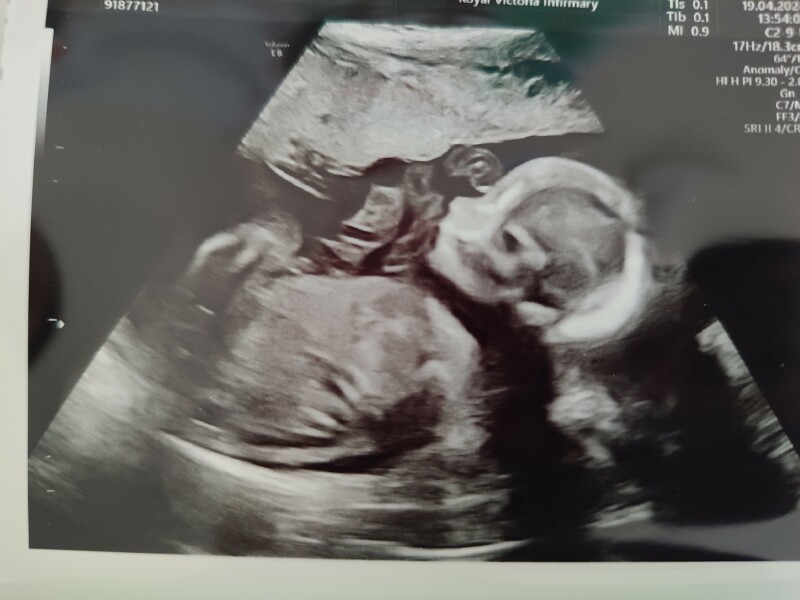

All good with the scan. We're having a girl! ☺️ And a very wriggly one too.

Congrats another girl, ours is a wriggler too!! Can't wait to see her again a week on Tuesday, I'll be 20+4 🩷